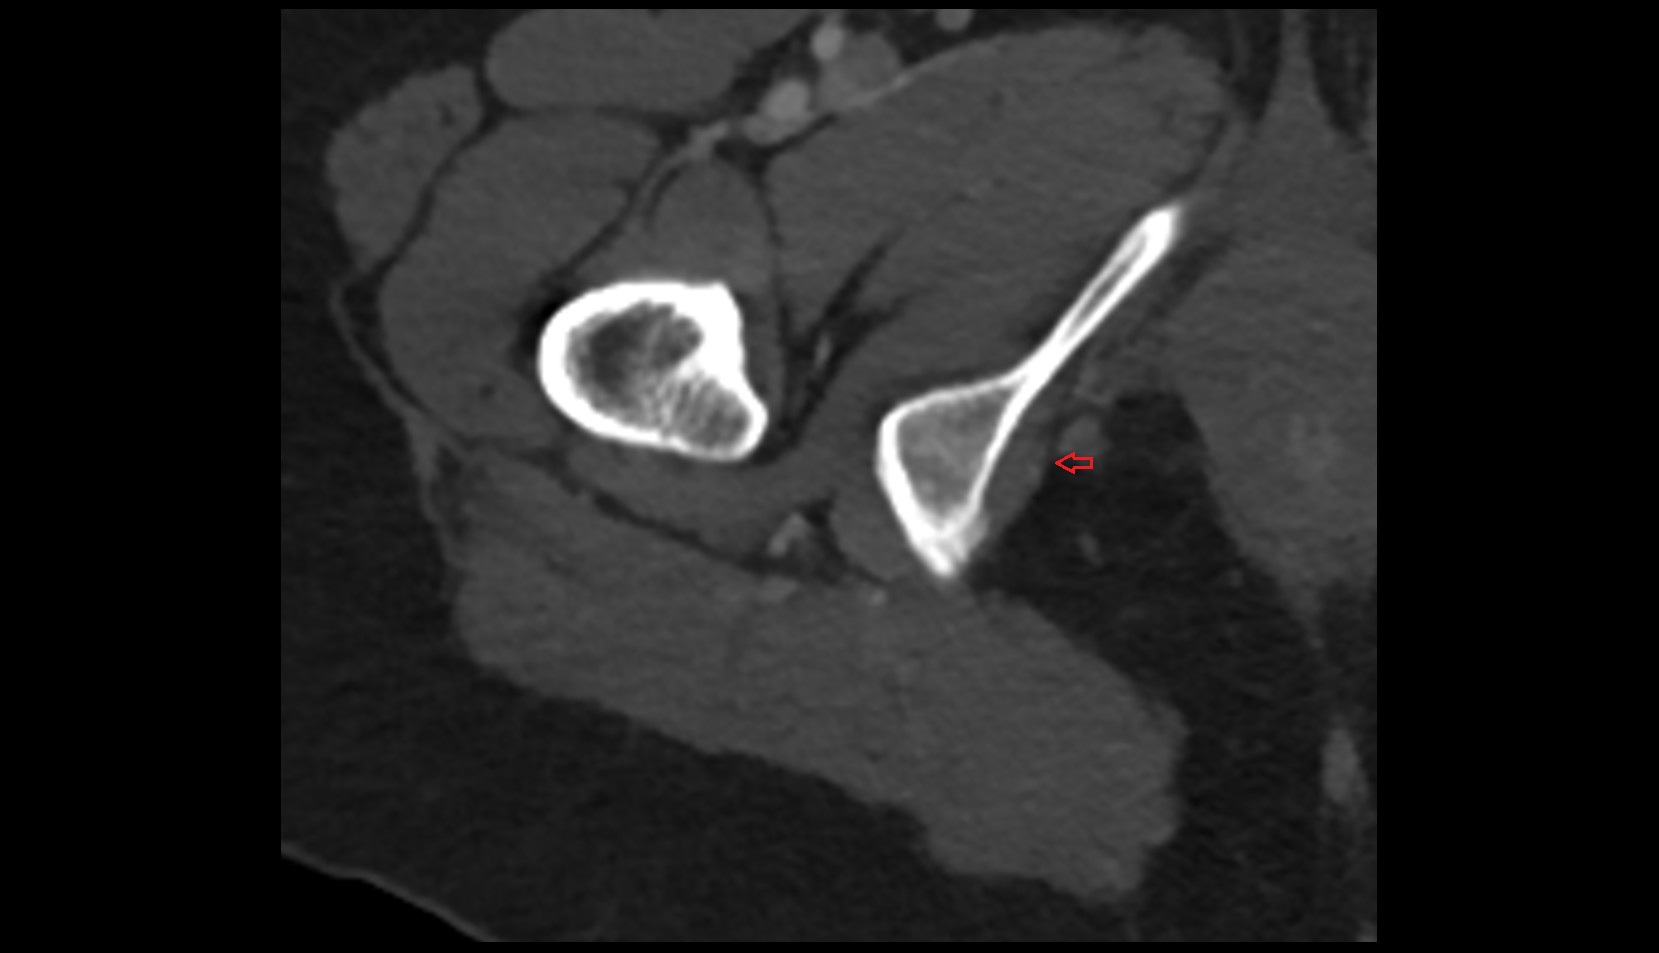

- Hip joint

- Head of femur

- Neck of femur

- Greater trochanter

- Lesser trochanter

- Acetabulum

- Acetabular labrum

- Articular capsule of hip joint